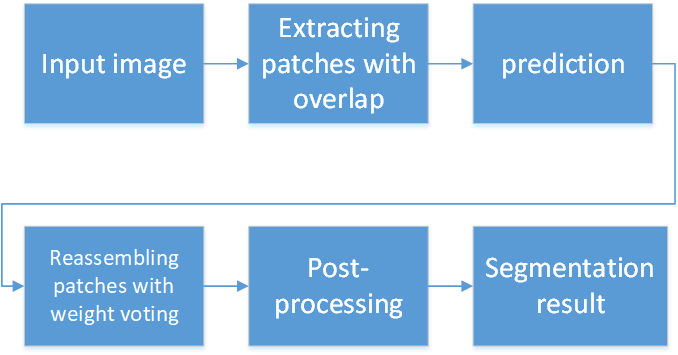

Our nuclei segmentation method adopts an end-to-end deep learning framework. The only preprocessing procedure is image color normalization. In the training phase, without extracting any features, even the H-channel, we directly apply the histopathology images in normalized RGB colors to the deep neural network to train the nucleus-boundary model. During the testing phase, the prediction result of raw normalized images yielded by the nucleus-boundary detector shows clear inside nuclei area and the boundaries. At last, we will obtain the area of each nucleus via a simple, fast and parameterless post-processing procedure. Fig.2 shows the procedure to segment nuclei from color normalized images in our algorithm.

II-C4 Extra-large Image Segmentation Using Overlapped Patch Extraction and Assembling

Current medical image segmentation algorithms based on U-net and its derivatives has an unsolved problem for segmenting extra-large high-resolution histopathological images: due to the limited memory of the GPU, it is possible to feed the whole slide image into the deep neural network. It has to be cut into patches and perform patch-wise training and prediction. However, there is no reported solution for deal with this issue.

With close examination, we found the the main issue of U-net algorithm on patch-based segmentation is that the prediction at the border area is not accurate as demonstrated in 11. Here we propose an overlapped patch extraction and assembling method. The patches are extracted by sliding window with a stride. For assembling, a vote mechanism is applied to predict each pixel using

where is the final prediction of the pixel at position (i,j) in an image. means the position of it in the patch.